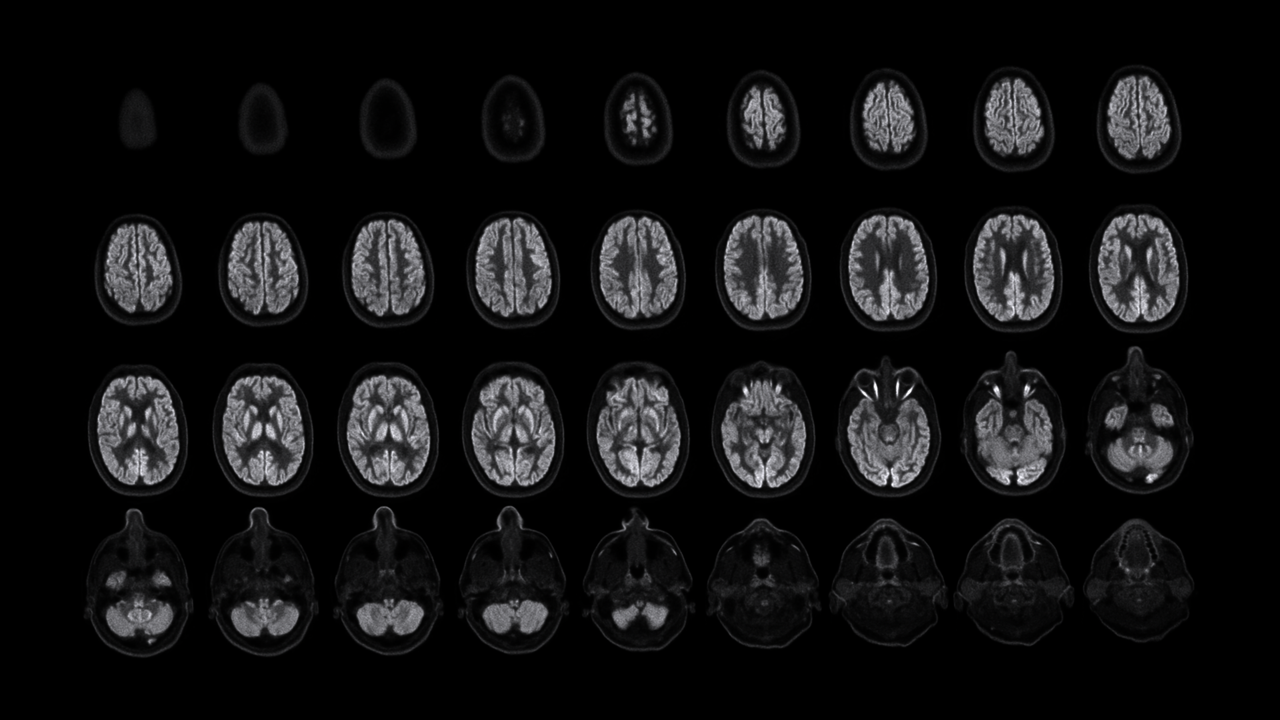

搭载长达50cm的轴向视野,可捕捉到从头顶到肩部区域的完整图像,确保其能够监测该区域的血管和示踪剂输送到大脑的动态情况,这一卓越性能助力NX成为脑科学领域研究强有力的工具。

NeuroExplorer (NX) 产出到从头顶到肩部区域的完整图像